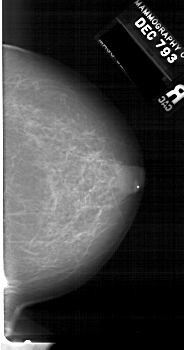

A_1513_1.LEFT_CC

LEFT_CC LINES 6586 PIXELS_PER_LINE 3421 BITS_PER_PIXEL 12 RESOLUTION 43.5 OVERLAY

FILE: A_1513_1.LEFT_CC.OVERLAY

TOTAL_ABNORMALITIES 1

ABNORMALITY 1

LESION_TYPE CALCIFICATION TYPE PLEOMORPHIC DISTRIBUTION CLUSTERED

ASSESSMENT 4

SUBTLETY 1

PATHOLOGY BENIGN

TOTAL_OUTLINES 1

BOUNDARY